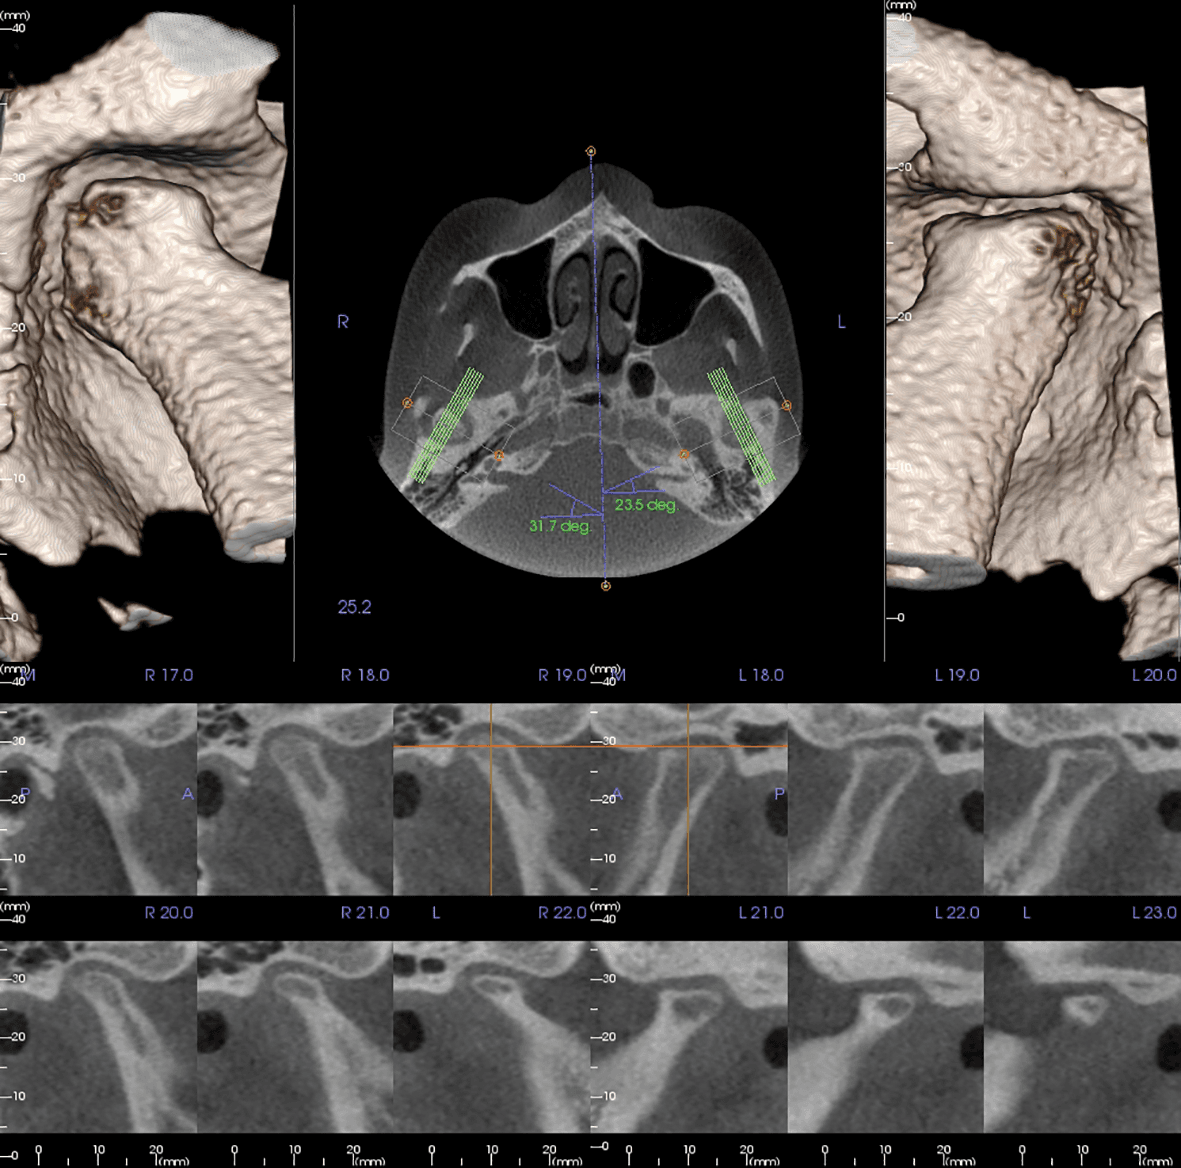

Osteoid has been a market leader developing the most advanced 3D rendering software for both medical and dental specialists for more than ten years. Invivo6 Plus, our latest version, maintains an intuitive user interface while delivering a wide range of diagnostic capabilities to provide the best patient outcomes. Invivo6 Plus lets you work work with scans from virtually any CBCT or CT device and supports a number of dental, orthodontic, endodontic and radiological applications.